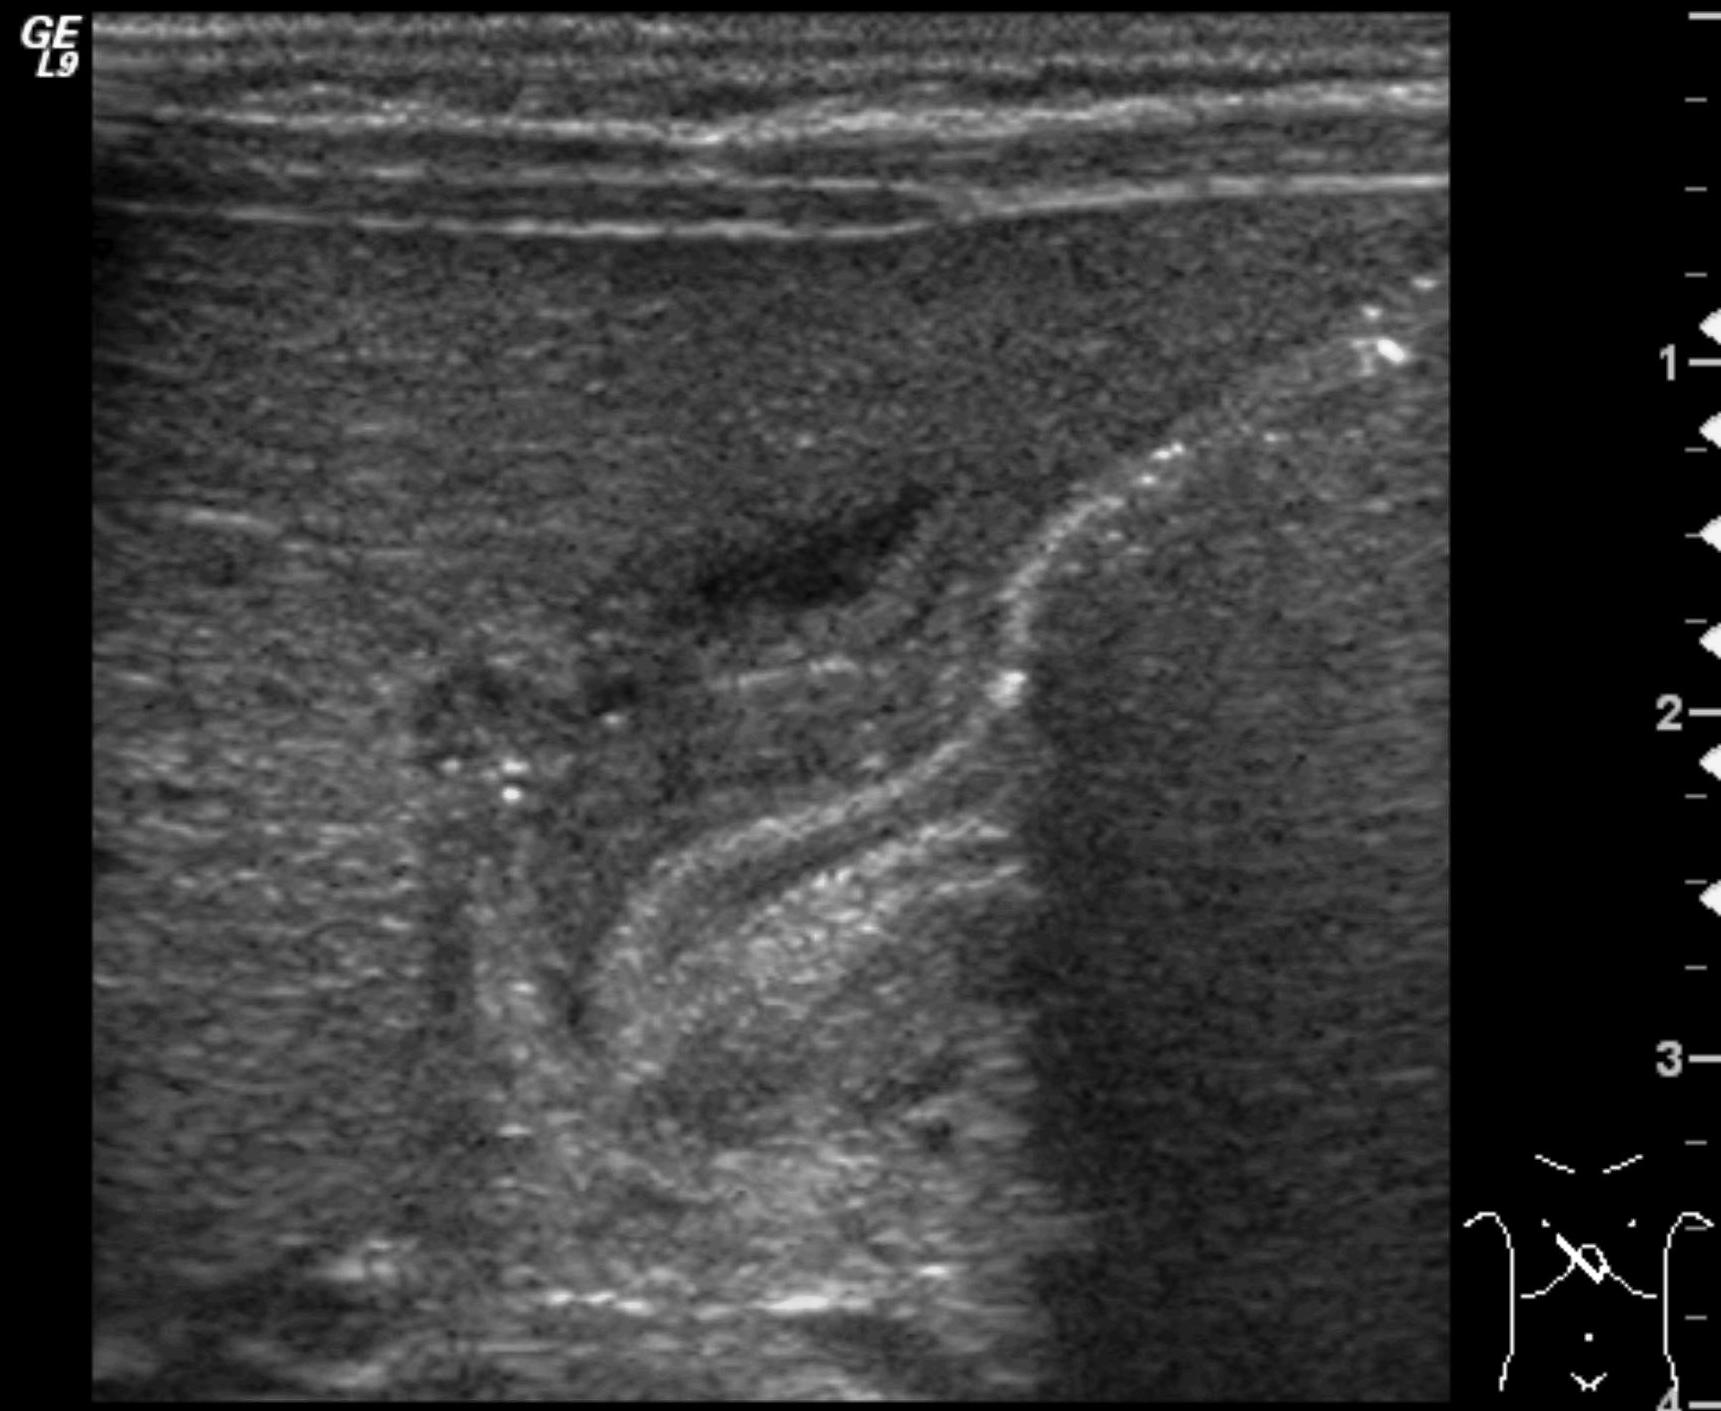

Uretropelvic obstruction (UPO). Uretropelvic junction stenosis can be an acquired or an innate state, with different degrees that lead to the dysfunction of excretion of urine from the pyelon to the proximal ureter. It is the most frequent form of obstructive uropathy. US examination even at prenatal states can diagnose the urinary tract dilatation that can be uni- or bilateral, always without ureter dilatation.

Image

22.The calices and the pyelon of the kidney are markedly dilated, the parenchyma is thinner. Severe hydronephrosis. The ureter is not visible. Pyelouretral stenosis.